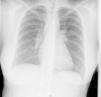

Como pruebas complementarias, se solicita una analítica, donde se objetiva una anemia con un hematocrito de 27,7% (vn 36-45) y una hemoglobina de 9,4g/dl (vn 12-16); normocítica y normocrómica, junto con una cifra de plaquetas de 540.000 (vn 130-450). Se realiza un estudio de la anemia, objetivándose un déficit de hierro (Fe: 18; vn 37-145) con ferritina, vitamina B12, ácido fólico y proteinograma normales, y un frotis de sangre periférica en el que solo destaca una discreta basofilia. En el resto de los estudios analíticos se objetiva asimismo un hipotiroidismo subclínico, con una TSH discretamente elevada y hormonas tiroideas normales que, consultado con el servicio de endocrinología, no precisó tratamiento sustitutivo. No se observan leucocitosis ni desviación izquierda y las funciones renal y hepática, los iones y la coagulación son normales. Como reactantes fase aguda, presenta una velocidad de sedimentación globular de 110mmHg y una proteína C reactiva 28,8mg/dl. En el estudio de autoinmunidad presenta un factor reumatoide de 24 U/l, anticuerpos antinucleares 1/80, siendo los anticuerpos anticitoplasma de neutrófilo negativos. La enzima convertidora de angiotensina (ECA) se encuentra dentro de valores normales (ECA: 38; vn 18-58). Se solicitan hemocultivos, que fueron negativos, y un sedimento de orina, que fue normal. Las serologías solicitadas, hepatitis, virus de la inmunodeficiencia humana, rubéola, citomegalovirus, virus de Epstein-Barr, Toxoplasma, Treponema pallidum, Borrelia, Mycoplasma y Chlamydia, fueron negativas. Se realiza una radiografía de tórax donde se visualizan adenopatías hiliares bilaterales (fig. 2). Para descartar una posible tuberculosis se solicitan una prueba de Mantoux que fue negativa y auraminas en orina seriadas, que también fueron negativas.

Se realiza una TC de alta resolución, que resulta compatible con una sarcoidosis de grado I (adenopatías hiliares bilaterales y en mediastino) (fig. 3). En la biopsia transbronquial se objetiva un componente inflamatorio y en el lavado broncoalveolar existe un cociente de CD4/CD8 de 5,26, con un 80% de histiocitos, un 15% de linfocitos y un 5% de neutrófilos.